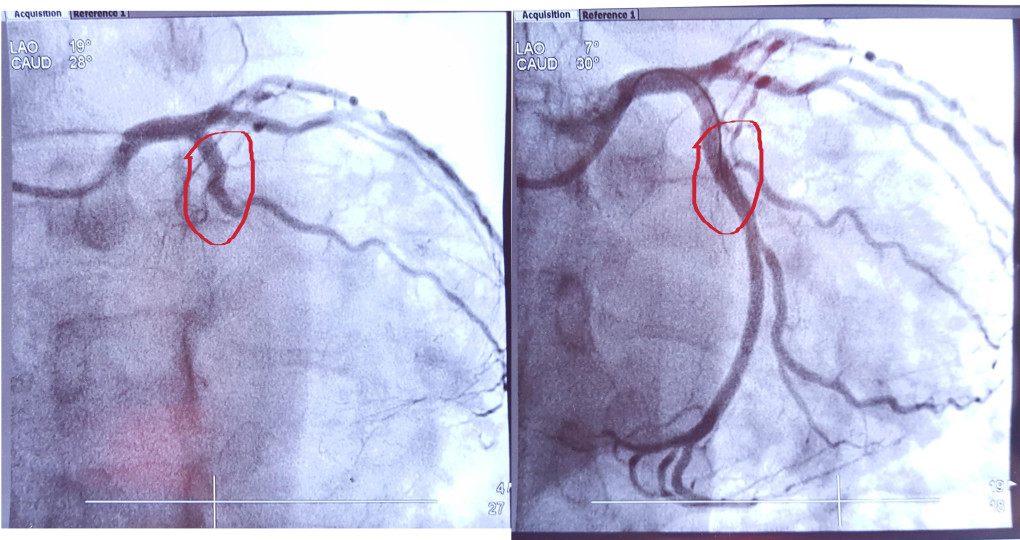

Efter operationen fik jeg de her to røntgenbilleder af sygeplejersken.

My heart - before the stentPå billedet til venstre, i området market med rødt, er den ene af de tre store kanspulsårer blodårer der forsyner hjertet med ilt lukket til af en blodprop. På billedet til højre ses det samme område få minutter senere, hvor blodproppen er fjernet og det indsnævrede område udvidet med ballon og sikret med stent.